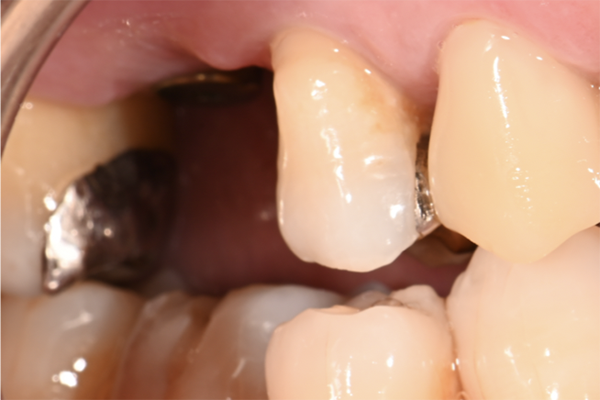

| 主訴 | 右上の奥歯を入れたい |

|---|---|

| 治療内容 | 右上第一大臼歯に対するインプラント治療 |

| 治療期間 | 4ヶ月 |

| 治療費 | 39万5千円 |

| 治療 リスク | インプラントの土台を入れた後最終的な歯が装着されるまで仮歯をしていただきます |